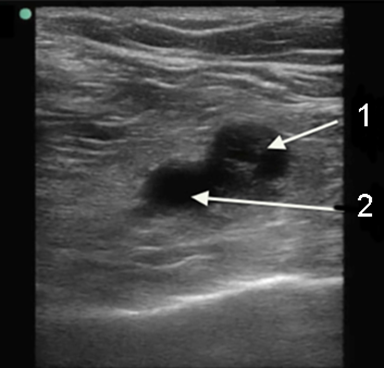

Imagen 2 de trombo en la vena poplítea

Vena poplítea/trombo

Arteria poplítea